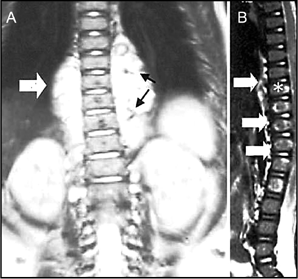

A 4-year-old girl was noted to have a birthmark over the thoracolumbar region at birth. Her mother had experienced a normal pregnancy, labor, and delivery. The lesion gradually expanded in size, with associated swelling of the underlying skin. The patient visited a peripheral health center where an initial diagnosis of a skin-covered lumbar mass suggestive of a subcutaneous lipoma was considered. At 8 months, the child developed progressive weakness of the lower limbs and urinary and fecal incontinence. Examination of the affected area revealed a conspicuous 10 × 12-cm port-wine stain and swelling covering the back, between T5 and T12 (Figure 1). There was no apparent bruit, thrill, or raised temperature. There was a soft underlying mass suggestive of a lipoma. The child had severe spastic paraparesis in the lower extremities, with a very limited ability to lift her limbs, no muscle contractions or atrophy, with marked bladder/fecal dysfunction. She was examined by magnetic resonance imaging. Plain x-rays revealed a widening of the spinal canal with features suggestive of spina bifida. A Doppler study revealed a high-flow arteriovenous malformation. A T1-weighted magnetic resonance imaging scan of the thoracic and lumbar spine revealed high and low signal intensity associated with the T9–L2 vertebral bodies and T9–L2 paravertebral regions; enlargement of the spinal canal was noted, and the spinal cord was noted to be compressed (Figure 2A and B). The findings suggested vertebral, paravertebral, and spinal angiomas, with lipomyelo-meningocele and compression of the cord. Ultrasonography of the abdomen was normal. The parents were reluctant to undergo arteriography. Consequently, the patient was administered prednisolone p.o. at an initial dosage of 15 mg/d (2 mg/kg every 24 hours in divided doses, 4–6 hourly). Paraparesis partially improved with some regression of the port-wine stain. In view of the size of the underlying angioma and pressure effect, a consultation by pediatric neurosurgeons was performed. Endovascular embolization with surgical reduction of the lipomyelomeningocele was contemplated, but the associated risk and chance of recurrence/incomplete response proved to be a deterrent to the parents.

Figure 2

A) T1-weighted and B) gadolinium-enhanced magnetic resonance imaging scans revealing high and low signal intensity associated with the T9(*)–L2 vertebral bodies (suggesting vertebral angioma), T9–L2 paravertebral lesions (open arrows), and the T5–L3 spinal canal (arrowheads), suggesting a huge vascular malformation. Signal voids were obtained in the paravertebral angiomas, suggesting vascular malformation (arrows)